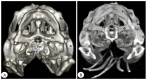

Anatomical Description of Loggerhead Turtle (Caretta caretta) and Green Iguana (Iguana iguana) Skull by Three-Dimensional Computed Tomography Reconstruction and Maximum Intensity Projection Images

The growing interest in reptiles has posed a challenge to veterinary clinicians due to the lack of a standardized system to perform anatomical studies similar to those used for dogs and cats. In this paper, we have attempted to describe, employing computed tomography and subsequent three-dimensional reconstructions, the normal anatomical features that comprise the skulls of two species of reptiles: the loggerhead turtle (Caretta caretta) and the green iguana (Iguana iguana). Computed tomography (CT) and subsequent image processing allowed the identification of the bony structures that comprise the head of these species. As a result, and based on previous articles, we propose the most significant anatomical differences and similarities between these species.